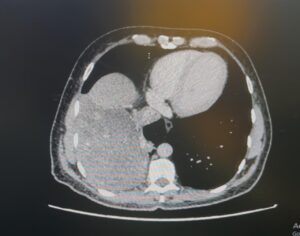

وكان المريض، البالغ من العمر 52 عامًا، قد راجع عيادات جراحة الصدر الخارجية بالمجمع وهو يعاني من أعراض مزمنة تمثلت في كحة مستمرة وارتفاع في درجة الحرارة. وبعد إجراء الفحوصات الطبية والأشعة المقطعية، تبين وجود ورم كبير يغطي النصف السفلي من تجويف الصدر، وملتصق بالفص الأوسط والسفلي من الرئة والحجاب الحاجز، ويلامس الوريد الأجوف السفلي الواقع أسفل القلب، مما زادت درجة الخطورة على حياته الصحية.

وعلى الفور تمت دراسة الحالة مع فريق جراحة الأوعية الدموية، حيث تم وضع خطة علاجية دقيقة تحسبًا لاحتمالية التصاق الورم بالأوعية الدموية الكبرى. وتم تنويم المريض بشكل عاجل وتجهيزه لنقله إلى غرفة العمليات الجراحية، ذلك لإجراء عملية باستخدام المنظار الجراحي للصدر مع إجراء فتحة جانبية للمساعدة في إخراج الورم نظرًا لضخامته.

وخلال العملية، تمكن الفريق الطبي من فصل الورم عن الرئة والحجاب الحاجز وكذلك عن القلب والوريد الأجوف السفلي دون حدوث مضاعفات، في إنجاز طبي يعكس كفاءة الكوادر الصحية بالمجمع.